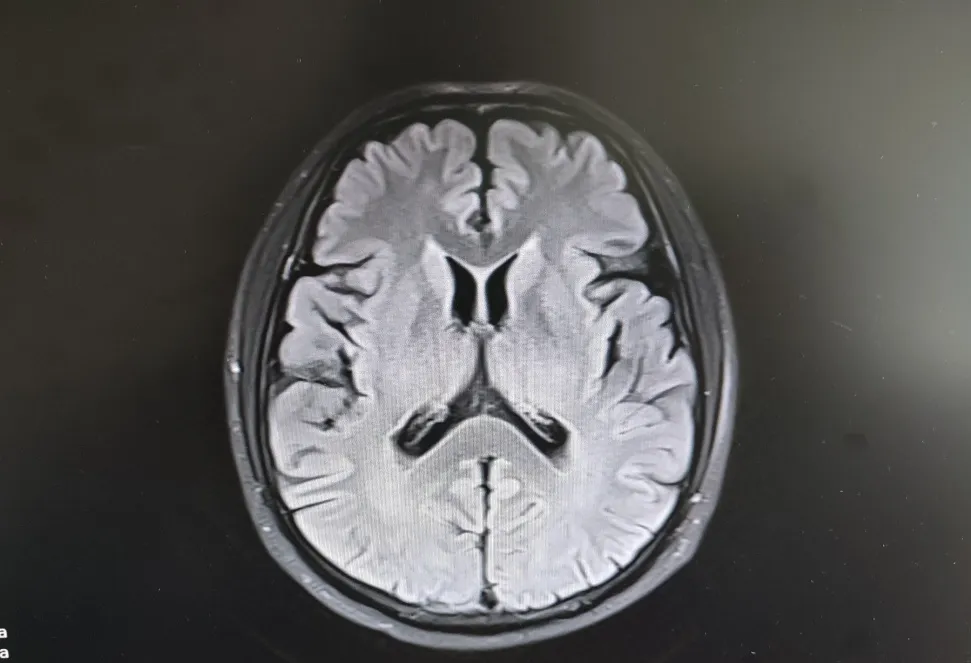

病房里还有另一位患者,来的时候情况更让人揪心:反应迟钝,表情呆滞,行动缓慢。头颅核磁显示脑萎缩明显,但查体发现肌张力、计算力、记忆力、定向力均正常,不符合典型血管性痴呆或阿尔茨海默病表现。

患者头部磁共振影像

凭着多年诊治疑难杂症的丰富经验,赵主任敏锐地意识到这“痴呆”可能是假象,背后另有隐情。他果断建议进一步做特殊感染筛查。果然,检查证实这位患者同样是感染了苍白密螺旋体!经过精准的抗感染治疗,奇迹发生了:患者的反应变快了,眼神灵活了,走路也恢复了正常步态。最终的诊断是“麻痹性痴呆”——一种由神经梅毒引起的、可治疗逆转的“痴呆”类型!